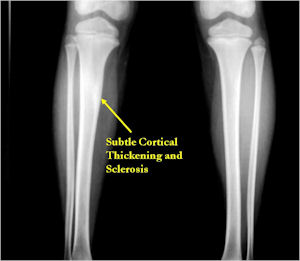

- Periosteal bone is solid, rarely lamellated

- Cortical and subperiosteal osteoid osteomas are usually associated with much more reactive sclerosis than medullary tumors

- The periosteal reaction is continuous and often appears as cortical thickening (benign appearing reaction)